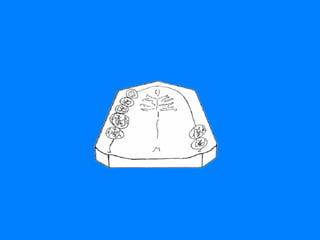

CLASE IV ZONA EDENTULA UNICA BILATERAL ANTERIOR A LOS DIENTES  NATURALES REMANENTES EN ESTA SITUACION DE EDENTICION PARCIAL LA EXTENSION DEL REBORDE RESIDUAL TAMBIEN INFLUYE EN EL ESTUDIO BIOMECANICO QUE SE DEBE ESTABLECER ANTES DE REALIZAR EL DISEÑO DE LA RPR

CLASE IV LIMITA CION 13-23

CLASE IV LIMITACION 16-23

CLASE IV LIMITACION 16-26

CLASE IV LIMITACION 34-46